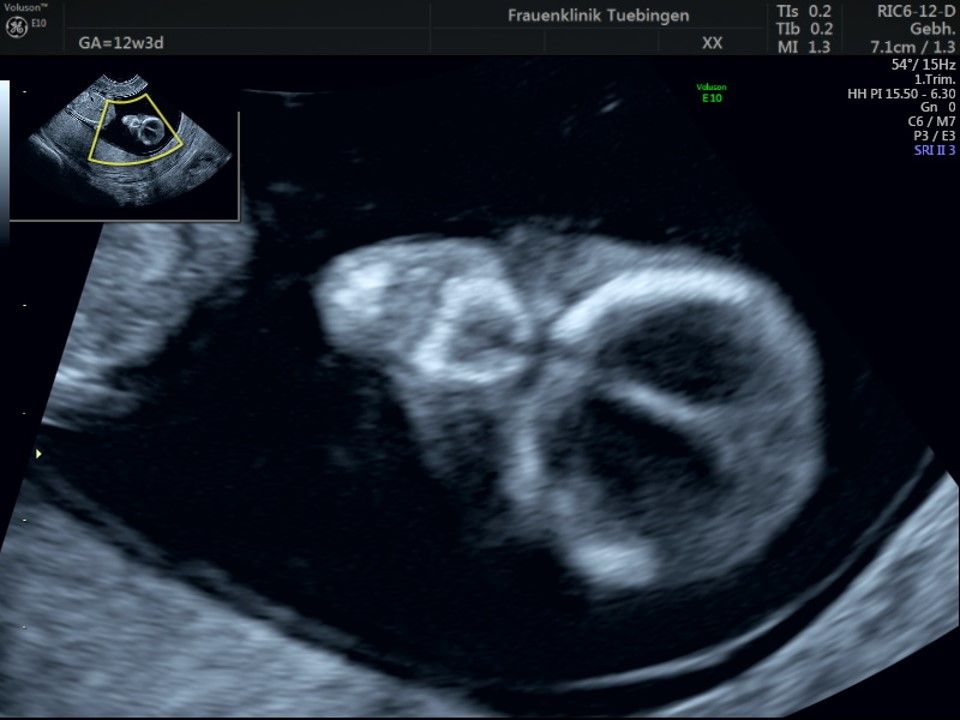

Im Rahmen des Ersttrimester-Screenings untersuchen wir die Organe des Feten mittels Ultraschall. Dabei machen wir auch gerne ein Bild für Sie.

Obwohl der Fet zu diesem Zeitpunkt erst zwischen 5 und 8cm groß ist, lassen sich bereits etwa die Hälfte aller schwerwiegenden Fehlbildungen erkennen bzw. ausschließen. Sollten wir eine Auffälligkeit sehen, werden wir mit Ihnen den Befund und das weitere Vorgehen ausführlich besprechen.

Die eigentliche Organuntersuchung findet um die 20.SSW (zweites Screening) statt. Das Ersttrimester-Screening und das zweite Screening sind sich ergänzende Untersuchungen und ersetzen sich gegenseitig nicht.